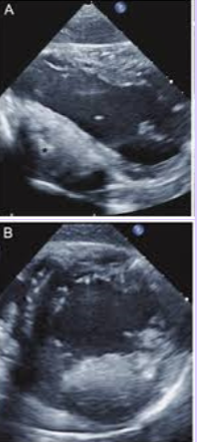

Mural thrombus

Only one surface is exposed to blood pool; other sides connected to cardiac wall.

Incidence for embolization and thromboembolic event is lowest.

Protruding thrombus

More than one surface of the thrombus is exposed to the blood pool.

<p>More than one surface of the thrombus is exposed to the blood pool.</p>

Mobile thrombus

Independent motion of part or whole thrombus.

Incidence for embolization and thromboembolic event is highest.

<p>Independent motion of part or whole thrombus.</p><p>Incidence for embolization and thromboembolic event is highest.</p>